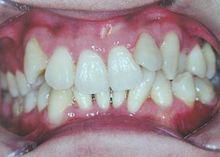

目前隨著材料學的迅速發展,一種玻璃纖維材料業已問世,並以其獨特的性能成功運用於口腔臨床。玻璃纖維具有輕、薄、高強度、有粘結性、生物相容性好、易操作、美觀等優點,見圖2。與金屬絲相比,玻璃纖維具有與牙釉質、牙本質相接近的彈性模量,其強度較高, 不易折裂。用這類材料製成的牙周夾板,具備良好的剛性和密合性,能有效傳導分散咬合力,減輕牙周組織的創傷,亦有效避免了反覆修補折裂的複合樹脂夾板的問題,可成功使用1年以上。

圖2玻璃纖維牙周夾板固定下前牙圖2 玻璃纖維牙周夾板固定下前牙。可見玻璃纖維表現出良好的美觀效果。玻璃纖維不僅強度和硬度高於常規使用的複合樹脂,還具有更大的彎曲強度,即使牙列擁擠、排列不齊,使用玻璃纖維進行牙周夾板固定,也可與牙面充分貼合,不影響美觀。